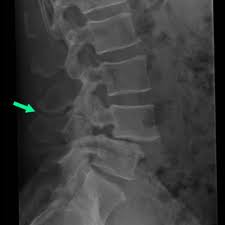

Grade 1 Anterolisthesis - Can One Avoid Surgery To Cure Grade 4 Anterolisthesis Of L5 S1 Region Dr Kodlady Surendra Shetty Youtube : Increasing grades denote worse slippage.. More specifically, the upper vertebral body slips forward on the one below. This refers to a less than 25% slippage of the l5 vertebra in relation to s1. The amount of slippage is graded on a scale from 1 to 4. Its severity can be graded by the meyerding classification and its etiology classified according to the wiltse classification. 0% to 25%, grade 2:

While grade 1 is mild with less than 25% slippage, grade 4 is severe with greater than 75% slippage. There are four grades of slippage: In grade iv, the slippage is more than 75%; Type 1) results from congenital abnormalities of the upper sacral facets or inferior facets of the fifth lumbar vertebra, and accounts for 14% to 21% of all anterolisthesis. A closer look at a vertebra that has slipped forward. Anterolisthesis is categorized according to the level of slippage. Images showing anterolisthesis in various grade level. The symptoms of anterolisthesis can vary greatly depending on the grade and the area affected.

Pain is often the first symptom. Grade 1 is less than 25% slippage, while grade 4 is more severe (75% or more). Retrolisthesis grades just like spondylolisthesis, the seriousness of a retrolisthesis is graded from 1 to 4 based upon the percentage of posterior or backward displacement of the vertebral body's foramen or neuroforamen. Grade 1 anterolisthesis of l4 on l5 secondary to severe facet arthrosis resulting in severe central canal stenosis and the buckloing of the nerve roots superior to this level. In grade iv, the slippage is more than 75%; Analysed the correlation between disc degeneration and the age, duration and severity of clinical symptoms and grade of vertebral slip. It is usually from grade 1, which is the mildest form, to grade 4, which is the most severe form. Its severity can be graded by the meyerding classification and its etiology classified according to the wiltse classification.

What are the symptoms of anterolisthesis? 0% to 25%, grade 2: Retrolisthesis grades just like spondylolisthesis, the seriousness of a retrolisthesis is graded from 1 to 4 based upon the percentage of posterior or backward displacement of the vertebral body's foramen or neuroforamen. This is basically another term for spondylolisthesis. Type 1) results from congenital abnormalities of the upper sacral facets or inferior facets of the fifth lumbar vertebra, and accounts for 14% to 21% of all anterolisthesis. In grade i1anterolisthesis, there is mild slippage that is less than 25%. This grading scale helps determine the severity of the condition and the treatment necessary. So, you will have only mild symptoms for the issue. 2 a study of dai l.y. Grade 1 anterolisthesis of l4 on l5 secondary to severe facet arthrosis resulting in severe central canal stenosis and the buckloing of the nerve roots superior to this level. There are four grades of slippage: Increasing grades denote worse slippage. Grade 1 anterolisthesis the grading and classification of anterolisthesis is based not on the severity of the symptoms experienced but quite simply on the amount of movement of one vertebra with regard to its adjacent neighbour.